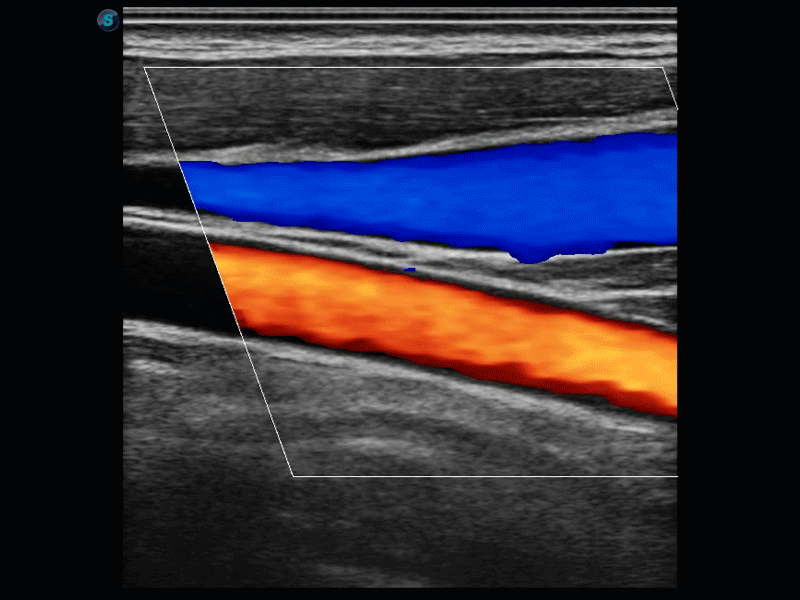

SR Flow高分辨率血流成像

高分辨率血流成像技术提高了对低速血流信号的检测能力。在提高空间分辨率的同时,也克服了血流外溢现象,为用户提供更加真实的血流动力学信息。

通过彩色血流和实时宽景相结合,可观察到完整的动静脉血流,方便医生检查。实时扫查过程中,如有任何操作失误也可以很容易地进行回扫擦除,而不会中断扫查。

临床图像